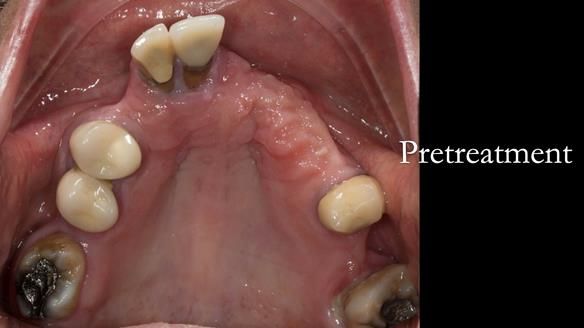

Aesthetically and functionally poor RPDs were replaced for Eileen, a 74 year old woman.

Referred to me by her general dental practitioner specifically for replacement RPDs.

Diagnoses

- Missing teeth in the upper and lower jaws

- Upper and lower metal based RPDs, poorly fitting, worn occlusal surface, reverse curve aesthetics, lacking support

- Poor dental appearance with reverse incisal curve

- The upper right central and lateral incisors with post crowns. Healthy and functionally secure but with poor appearance, contributing to the reverse curve.

- Moderate to heavily restored dentition with deep overbite (Class 2 div II)

- Yellowish lower front teeth with small amount of wear.

- The lower right canine (LR3) is worn with MOD cavity.